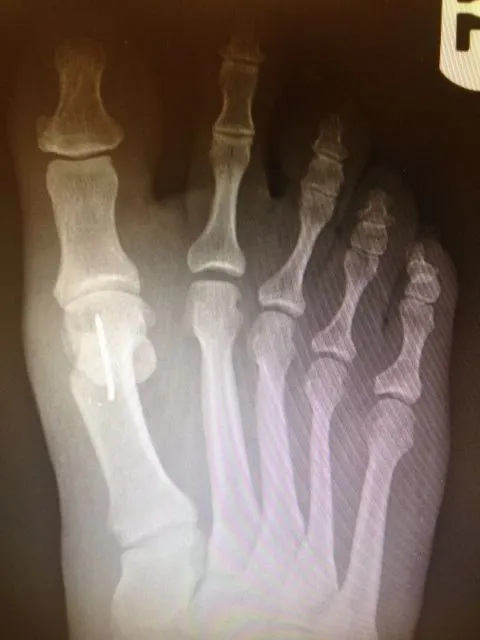

X-rays demonstrating correction of bunion deformity with the great toe deviated laterally (left image) and notice the position of the sesamoid bones which are the small round bones near the joint. The post-surgical film (right image) depicts alignment of the great toe significantly improved and the position of the sesamoid is underneath the 1st metatarsal head where it should be. This is a case where two surgical screws were used to fixate the correction.